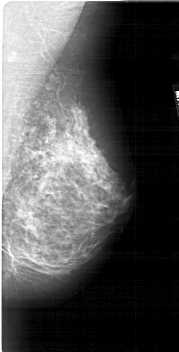

A_1883_1.LEFT_CC

LEFT_CC LINES 5356 PIXELS_PER_LINE 2671 BITS_PER_PIXEL 12 RESOLUTION 43.5 OVERLAY

FILE: A_1883_1.LEFT_CC.OVERLAY

TOTAL_ABNORMALITIES 1

ABNORMALITY 1

LESION_TYPE CALCIFICATION TYPE PLEOMORPHIC DISTRIBUTION CLUSTERED

ASSESSMENT 4

SUBTLETY 1

PATHOLOGY BENIGN

TOTAL_OUTLINES 1

BOUNDARY